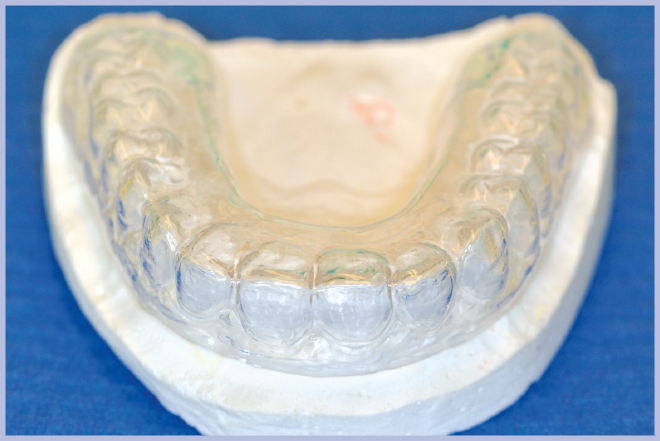

Quindi, con l’ausilio di una mascherina in resina trasparente, si è effettuata la registrazione occlusale; la mascherina è stata sfruttata anche per la demarcazione dei punti della nuova protesi da scartare in corrispondenza della posizione delle cappette (Figg. 7, 8).

- Fig. 7 – Mascherina in resina per la registrazione occlusale